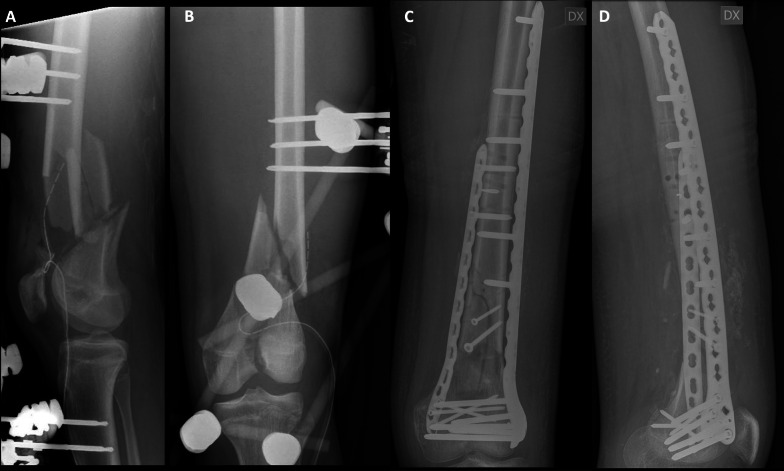

背景:股骨远端骨折是骨科医生面临的一个重大挑战,约占所有股骨骨折的5%。文献中最常报道的联合技术是双钢板技术和逆行钉入加侧钢板,即钉-钢板结构(NPC)。本研究的目的是比较双钢板或逆行内钉加侧钢板治疗33-C骨折的手术数据、生活质量和功能结果。材料和方法:根据加强流行病学观察性研究报告(STROBE)指南进行多中心回顾性观察性研究。诊断是基于AO分类,利用传统的放射学评估。根据患者接受的手术治疗将患者分为两组:NPC组包括接受钉子-钢板结构手术的患者,而Plate组包括接受双钢板手术的患者。结果:共纳入42例患者。鼻咽癌组26例,平均年龄58.4±18.8岁;钢板组16例,平均年龄61.3±16.4岁。在膝关节伸展恢复(p = 0.010)和股骨远端外侧角度(LDFA)方面观察到显著差异(p)。结论:在AO型C型股骨远端骨折中,与双钢板相比,钉钢板结构在膝关节功能和生活质量方面似乎具有明显更好的结果。解剖结果也显示出显著差异,特别是伸展间隙和LDFA。证据水平:III。

Background: Distal femur fractures present a significant challenge for orthopedic surgeons, accounting for approximately 5% of all femoral fractures. Among the most commonly reported combined techniques in the literature are the double-plate technique and the retrograde nailing plus lateral plating, the nail-plate construct (NPC). The aim of our study is to compare surgical data, quality of life, and functional outcomes in 33-C fractures treated with either double-plate constructs or a retrograde nailing plus lateral plate.

Materials and methods: A multicenter retrospective observational study was conducted in accordance with Strengthening the Reporting of Observational Studies in Epidemiology (STROBE) guidelines. Diagnoses were made on the basis of the AO classification, utilizing traditional radiological assessments. Patients were categorized into two groups on the basis of the surgical treatment they received: The NPC group comprised patients who underwent surgery with nail-plate construct, while the Plate group consisted of those who had surgery with double plating.

Results: A total of 42 patients were included in the study. The NPC group comprised 26 patients with a mean age of 58.4 ± 18.8 years, while the Plate group consisted of 16 patients with a mean age of 61.3 ± 16.4 years. Significant differences were observed in knee extension recovery (p = 0.010) and lateral distal femur angle (LDFA) (p < 0.001). Linear regression showed a significant influence from treatment choice on all the Knee Injury and Osteoarthritis Outcome Score (KOOS) subscales, as well as in all domains of the European Quality of Life Five Dimensions Five-Level Version (EQ-5D-5L), except for the Daily Self-Care domain.

Conclusions: Nail-plate constructs seems to lead to significantly better outcomes in AO type C distal femur fractures, compared with double plating, in terms of knee function and quality of life. Significant differences are shown also in anatomical outcomes, especially in extension gap, and LDFA.